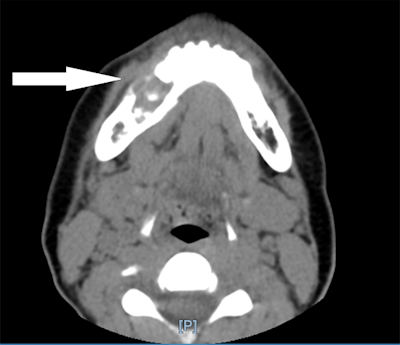

An oral surgery team was consulted, and a CT scan showed a lesion centered in the patient's right jaw with about 2.2 x 1.7 x 1.7 cm of erosion that went through the inner and outer cortex of the mandible. The erosion was centered on the roots of the right lower premolar teeth and first molar tooth with destruction of the second premolar tooth. This suggested a diagnosis of giant cell granuloma, and lab results from a biopsy sample confirmed it.